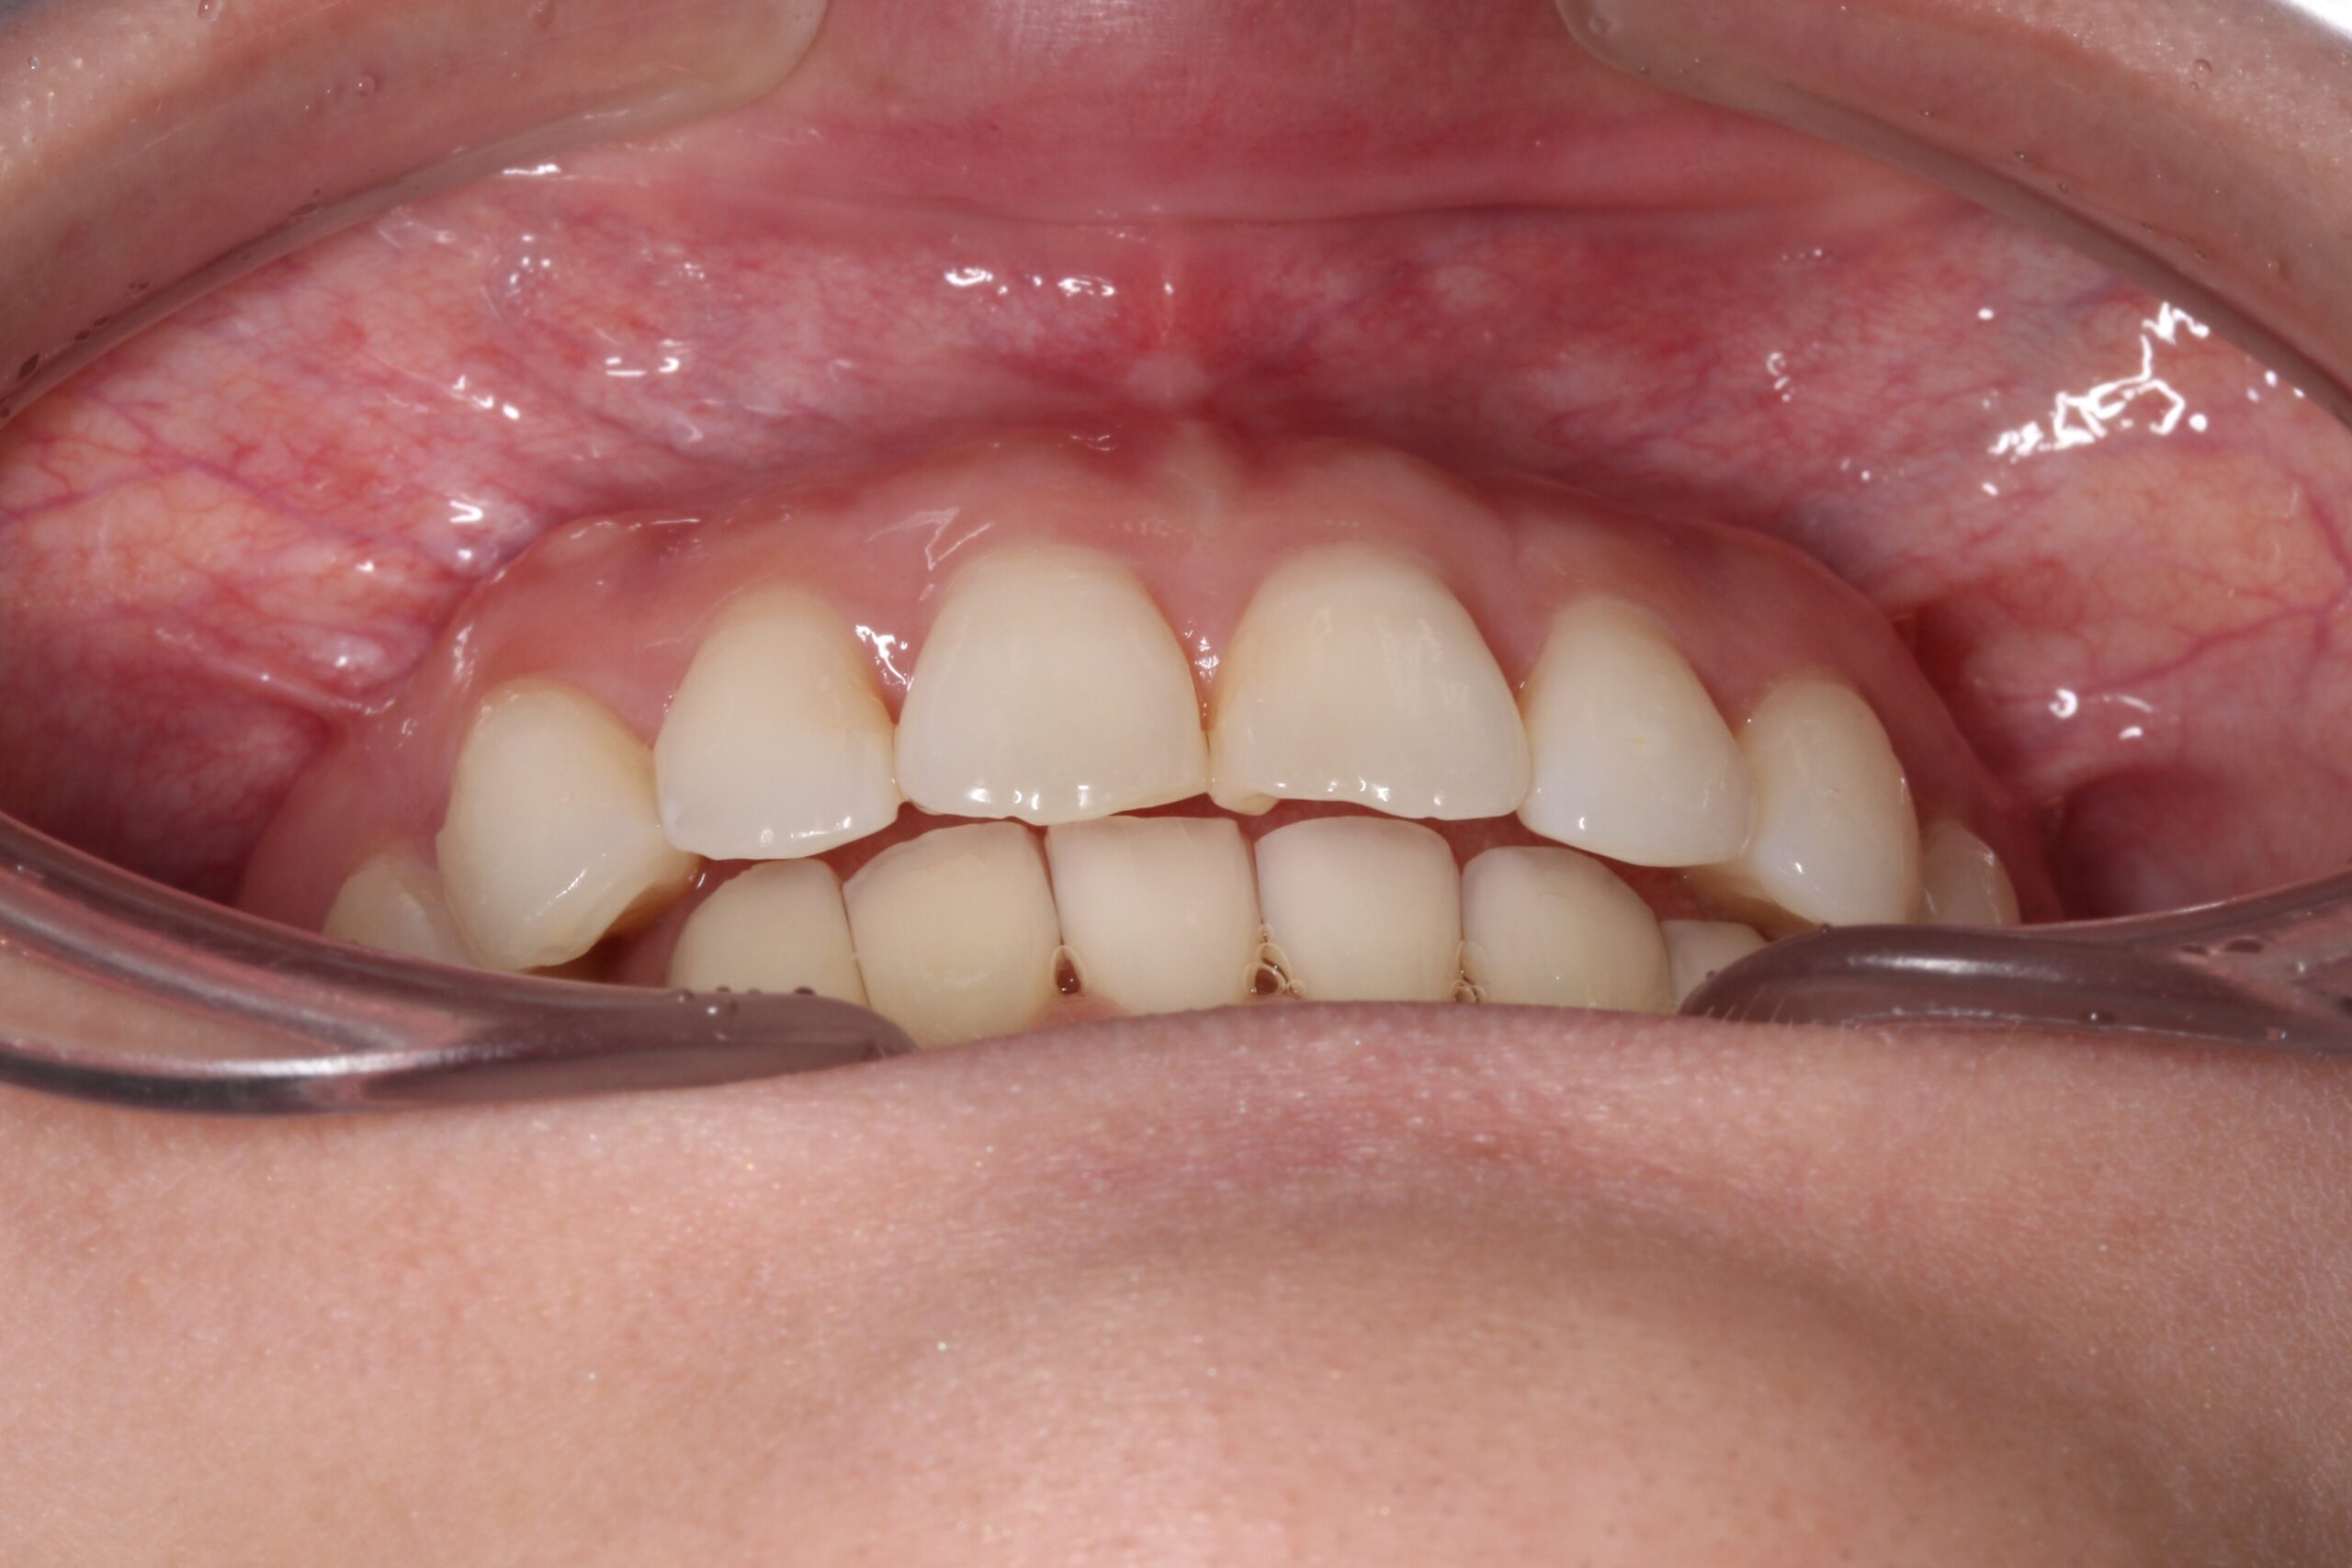

矯正術前:前歯部あおり

矯正術後:前歯部あおり

| 治療期間 | ・マウスピース矯正:16カ月 |

| 治療内容 | 上下の前歯のがたつきと捻じれを気にされており、矯正検査後叢生Ⅰ級と診断いたしました。 |